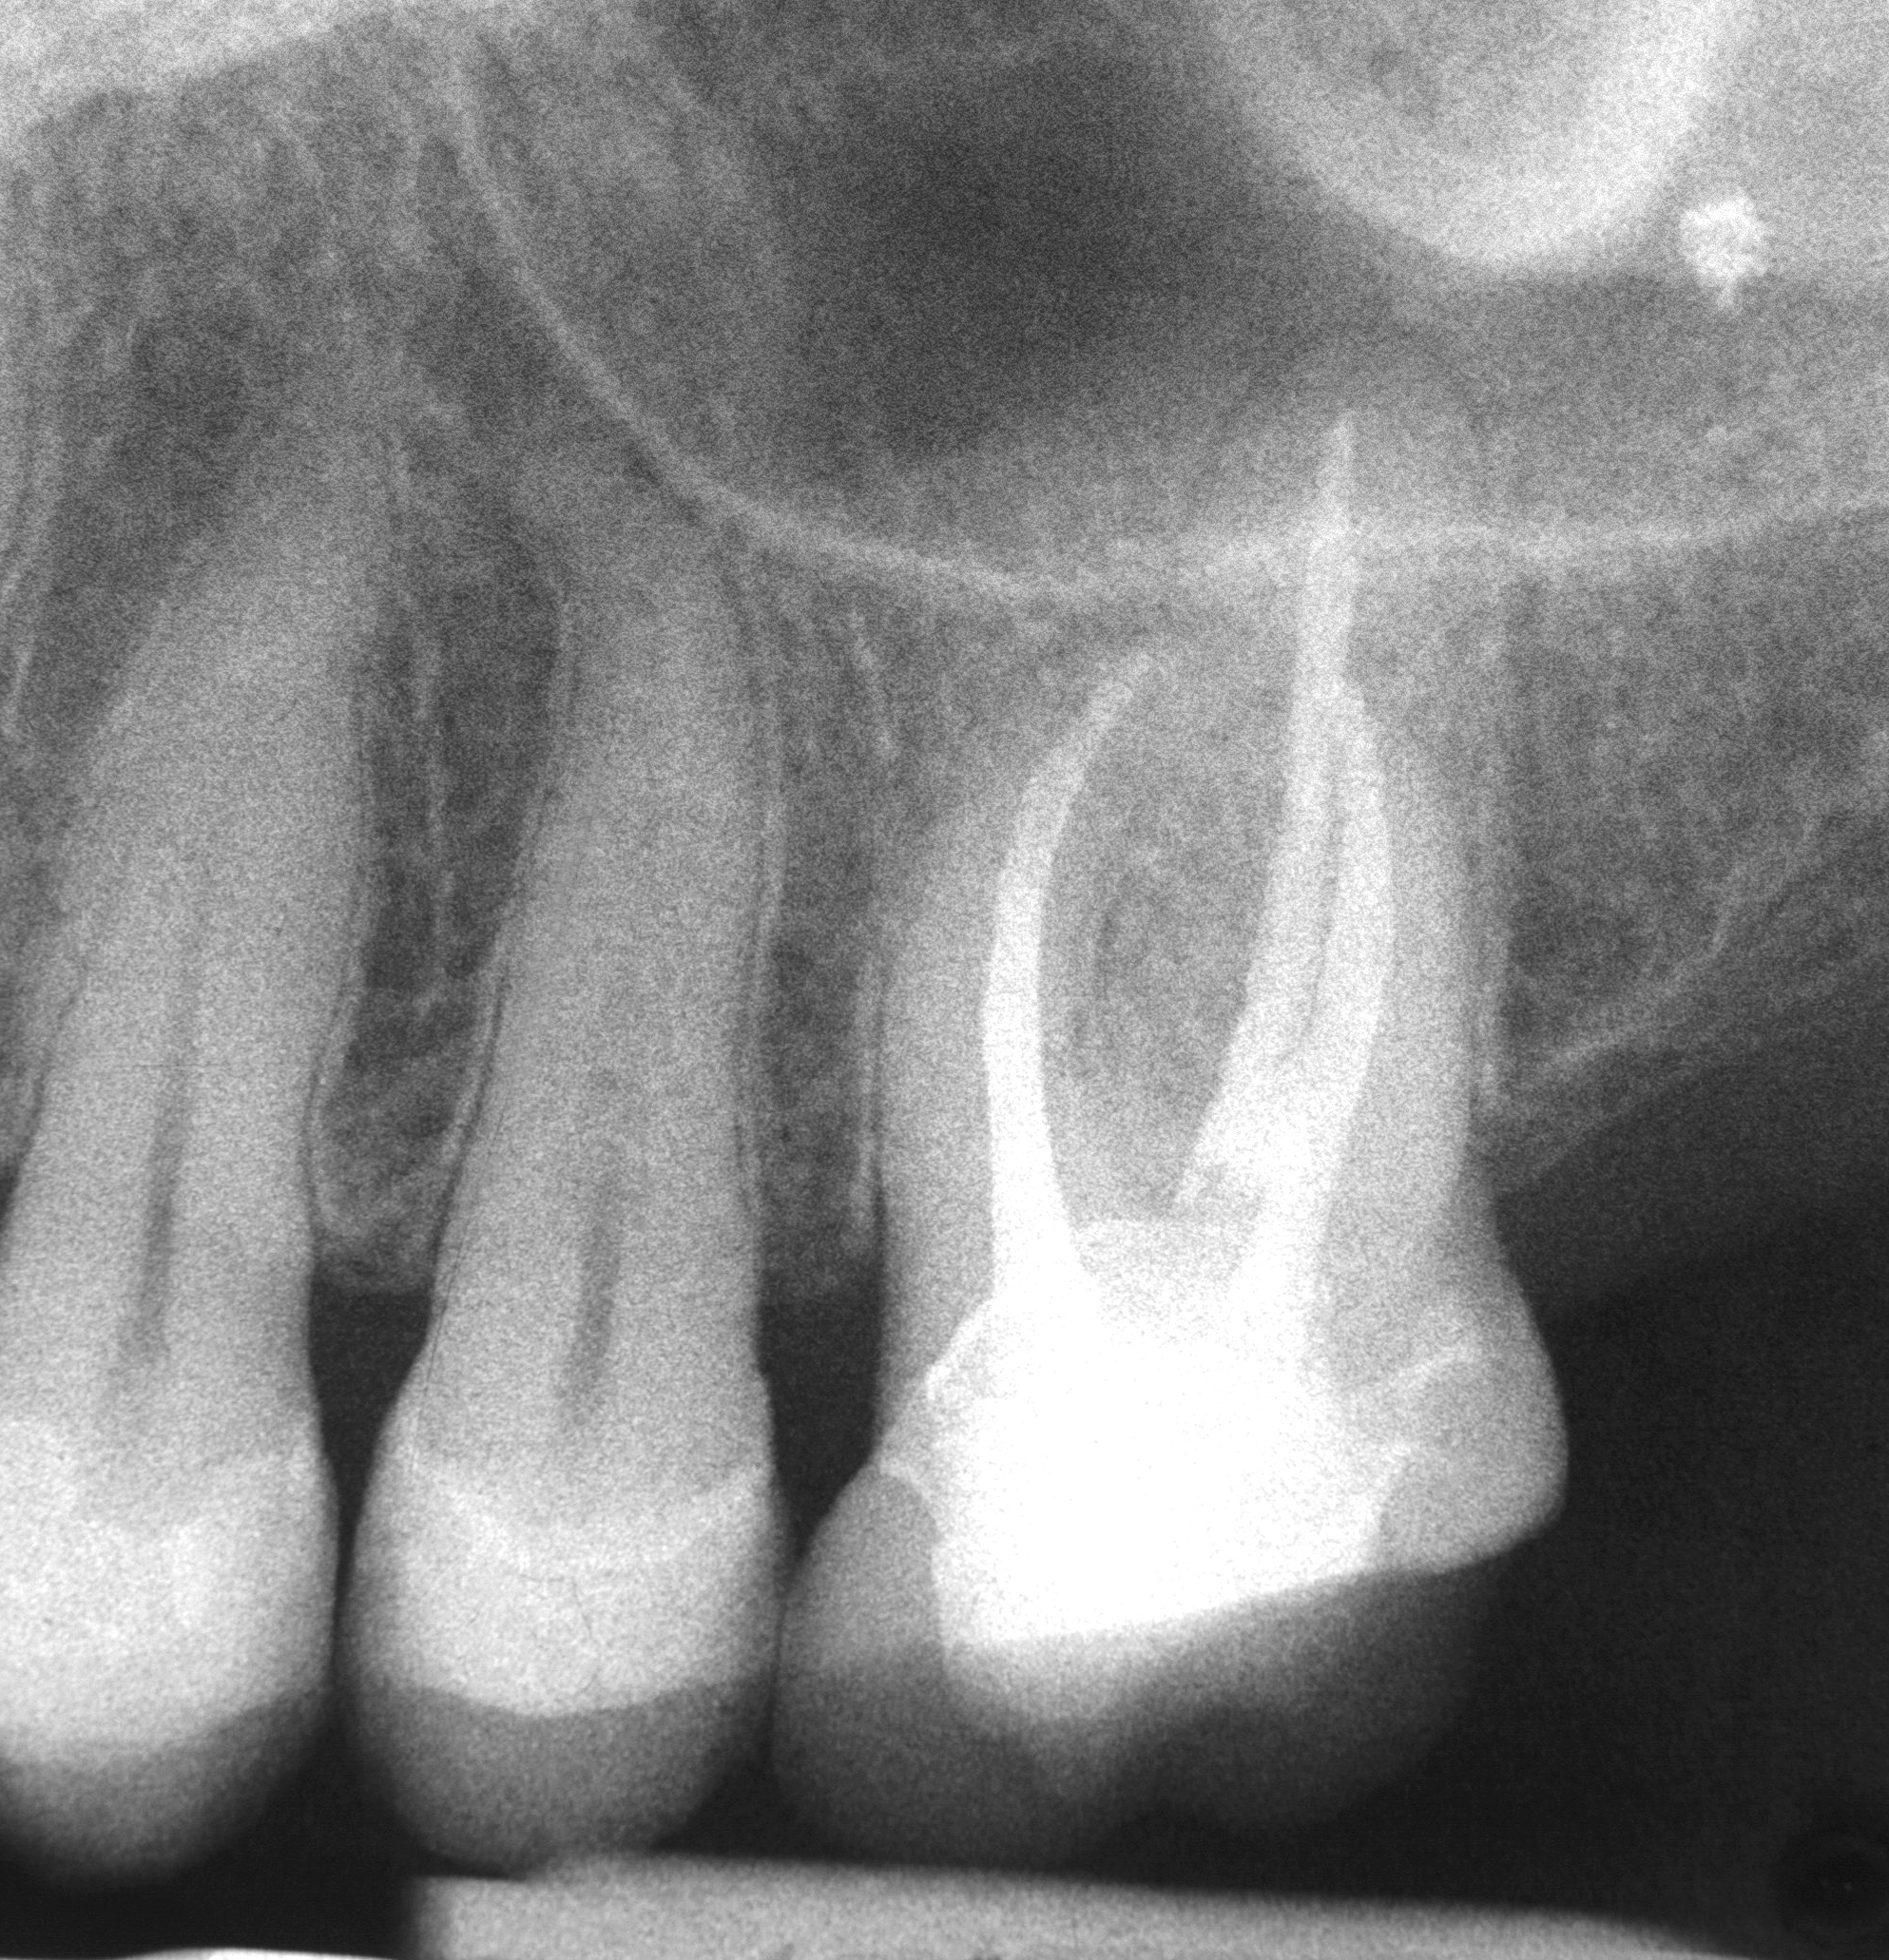

Die Verbindung zwischen endodontischen Erkrankungen und koronaren Herzerkrankungen (KHK) rückt zunehmend in den Fokus der Forschung. Studien zeigen, dass Patienten mit apikaler Parodontitis ein 1,4- bis 5-fach erhöhtes Risiko für kardiovaskuläre Erkrankungen aufweisen. Obwohl ein direkter Kausalzusammenhang bislang nicht belegt ist, verdeutlichen die Daten die Bedeutung einer erfolgreichen endodontischen Therapie – nicht nur für die orale, sondern auch für die systemische Gesundheit.

Eine apikale Parodontitis ist mit erhöhten Konzentrationen von Entzündungsmarkern im Blutplasma und gesteigertem oxidativem Stress verbunden. Diese Faktoren tragen zur Entwicklung von arteriosklerotischen Gefäßveränderungen bei, die letztlich eine KHK begünstigen können. Erfolgreiche Wurzelkanalbehandlungen oder Revisionen, die die endodontische Infektion eliminieren, führen nachweislich zu einer:

• Normalisierung systemischer Entzündungsmarker und Rückgang des oxidativen Stresses.

• Reduzierung des KHK-Risikos um bis zu 84 Prozent im Vergleich zu unbehandelten endodontischen Infektionen.

• Verminderung des Sterberisikos aufgrund einer KHK um bis zu 49 Prozent im Vergleich zu unbehandelten endodontischen Infektionen.